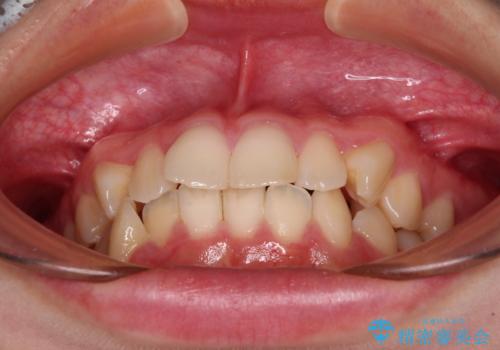

- 口元の閉じにくさを気にして来院された患者様です。

上下ともに歯列が前方に突出していたため、上下左右の第一小臼歯4本を抜去し、ワイヤー装置による矯正治療を行うこととしました。

舌の突出癖による影響もあったため、舌のトレーニングを並行して実施しました。

上下左右4本抜歯する場合には、通常2年から2年半ほどの期間を要しますが、舌のトレーニングをしっかりと行っていただいたことで、1年9ヶ月で終了することができました。